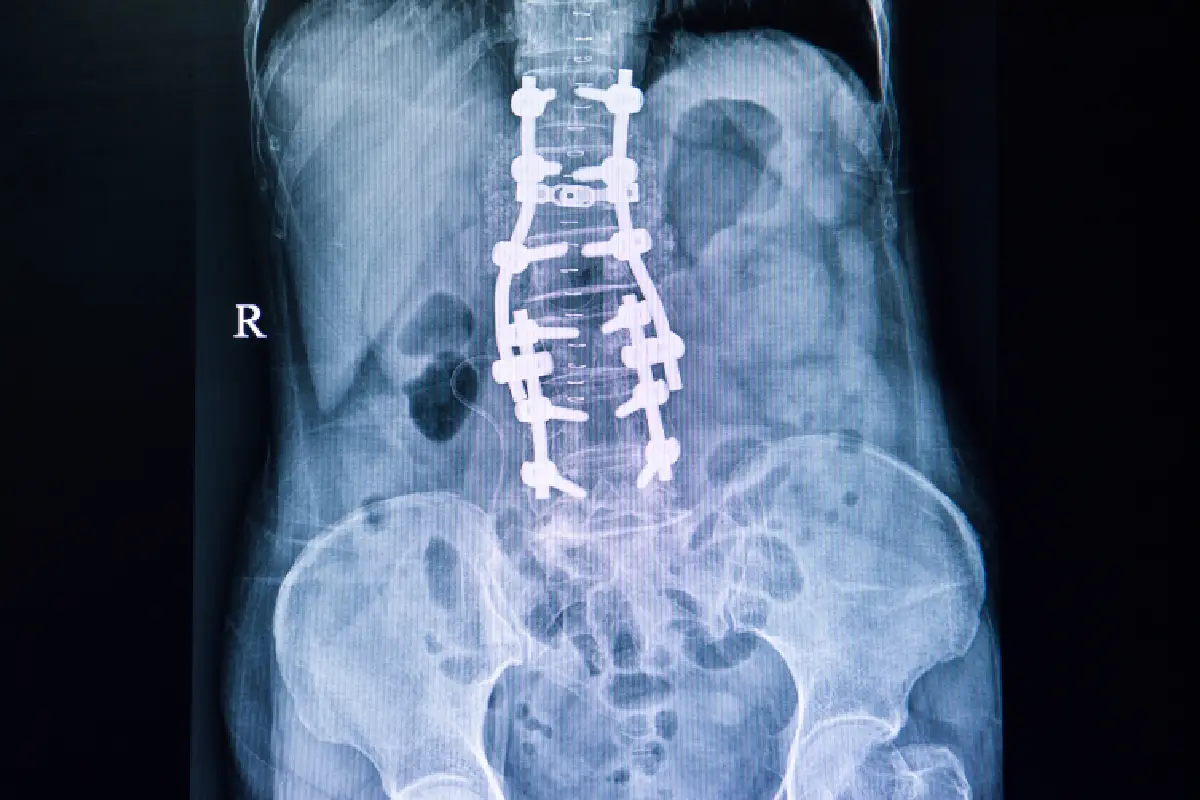

Scoliosis Surgery

Corrective scoliosis surgery realigning curved spine, improving posture, reducing pain, and preventing further progression.